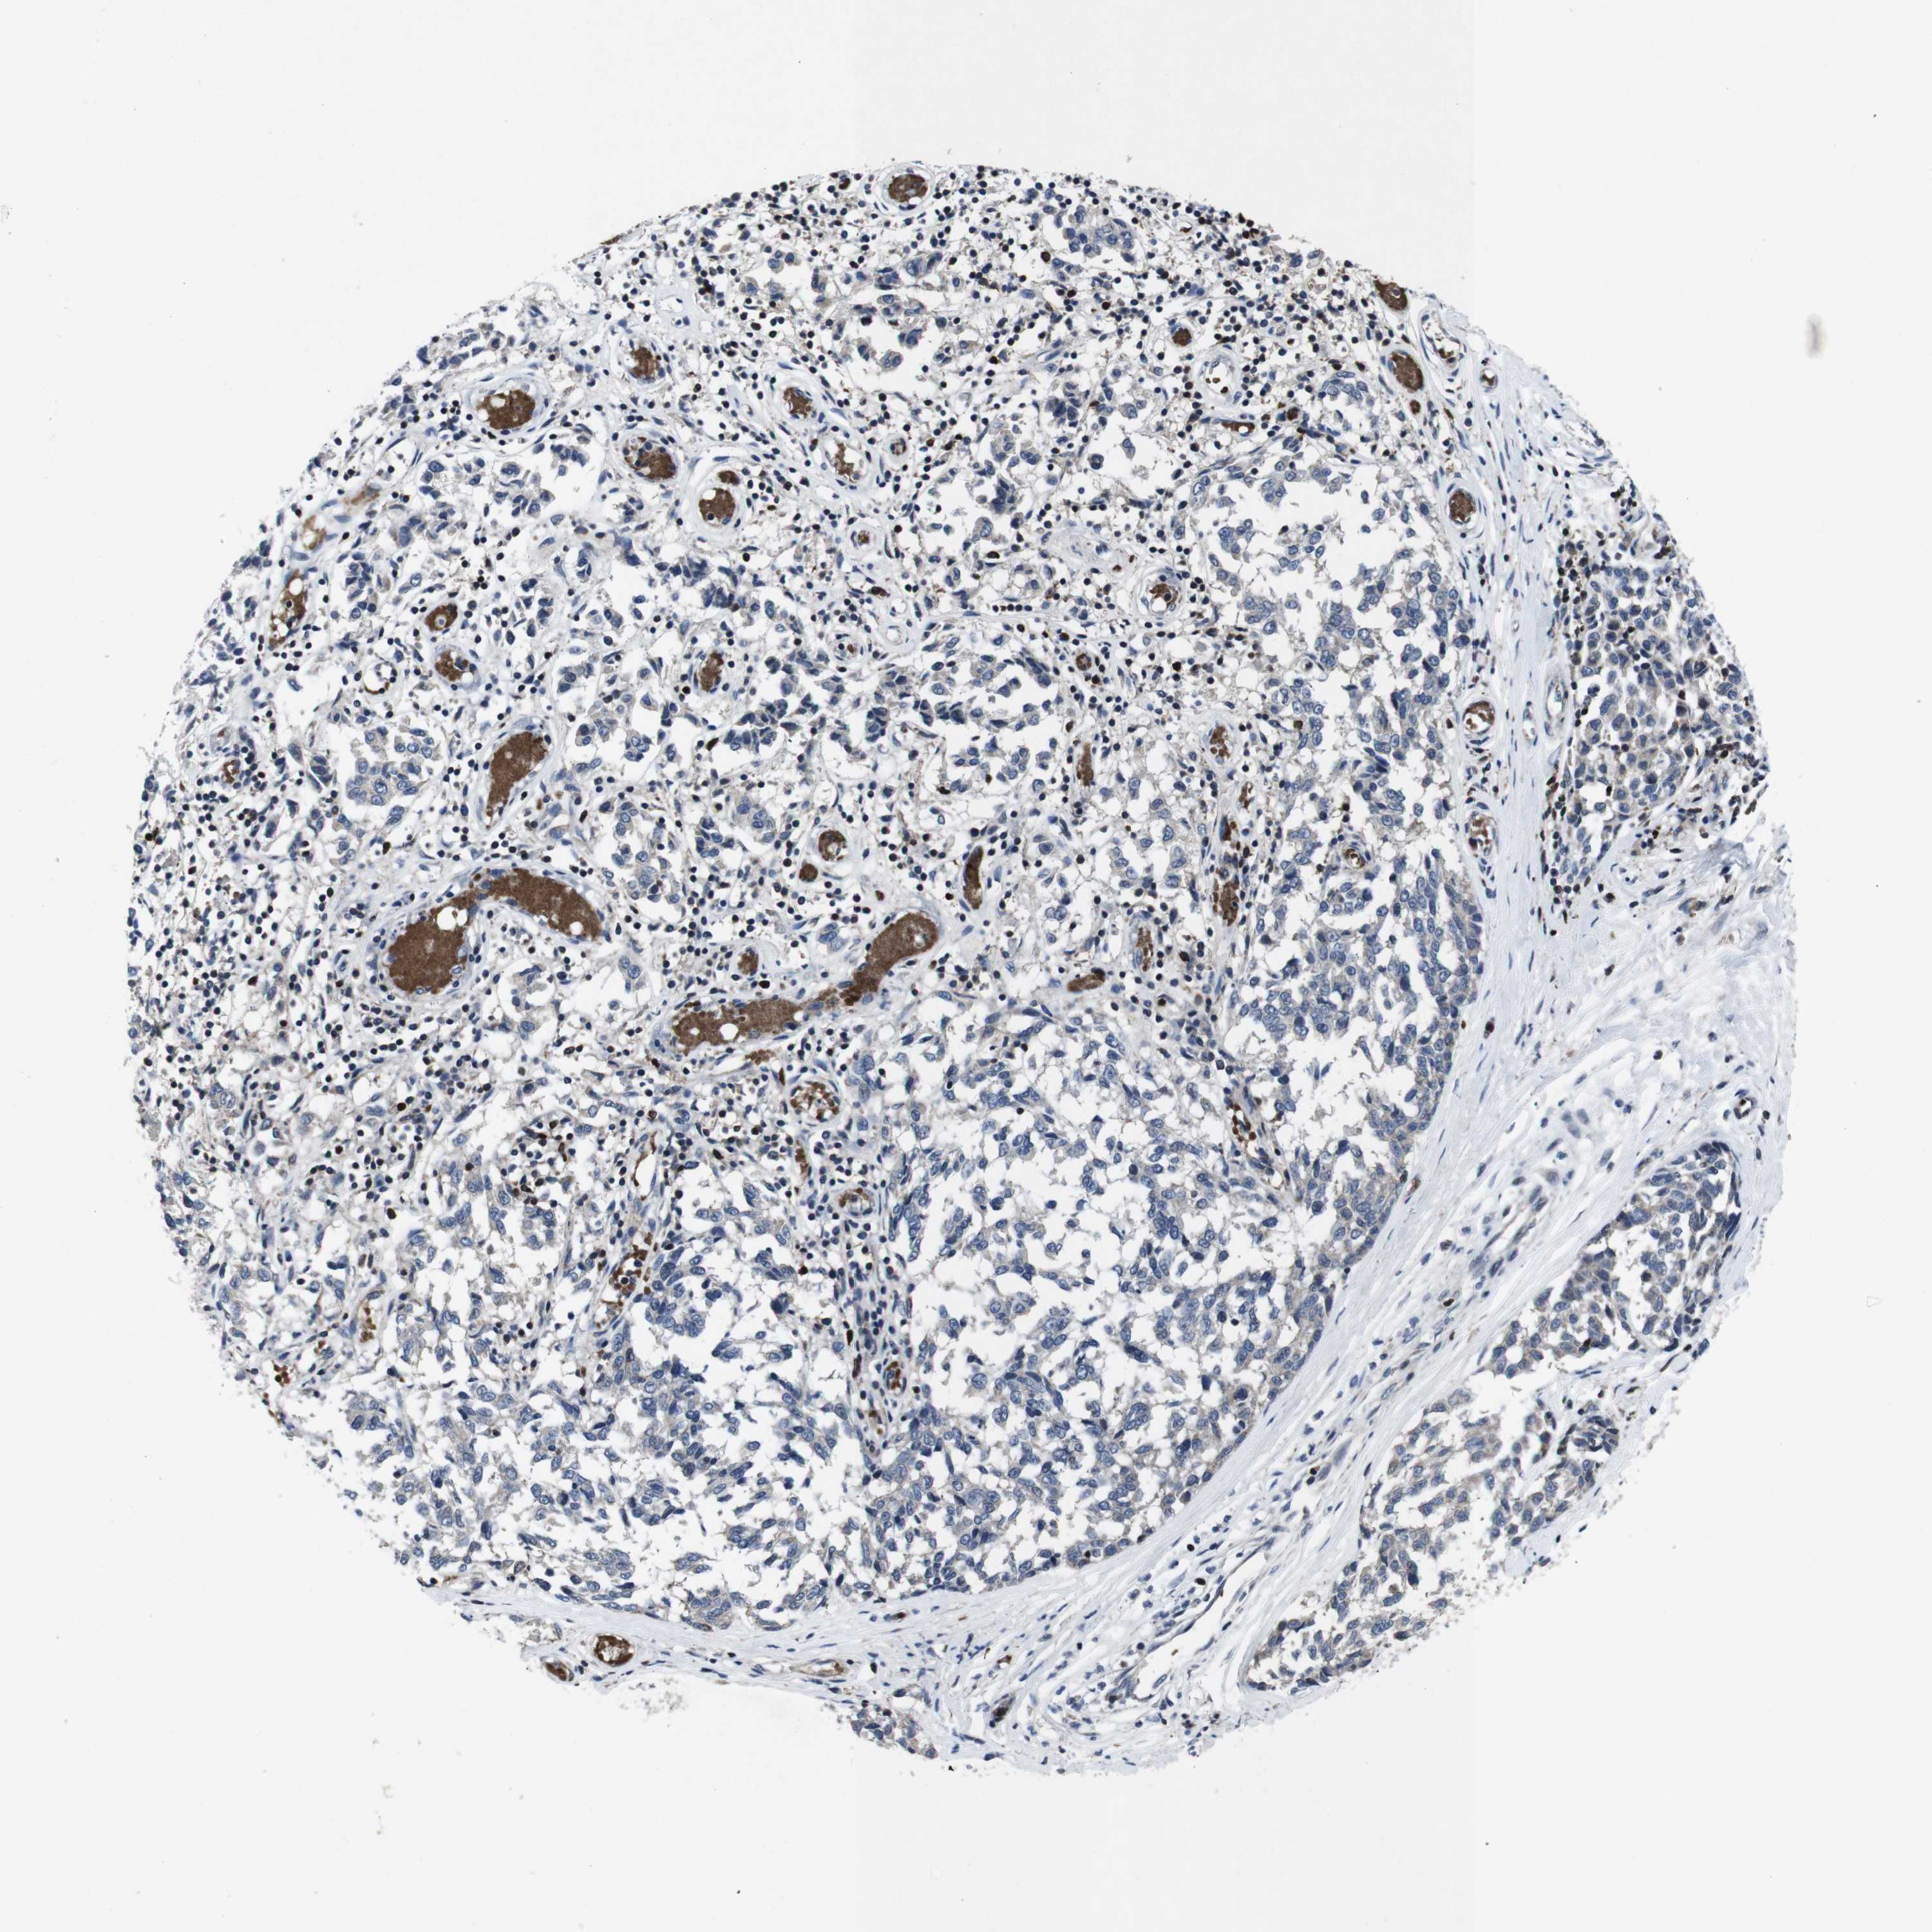

MELANOMA - Protein expressioni

A mouse-over function shows sample information and annotation data. Click on an image to view it in a full screen mode. Samples can be filtered based on level of antibody staining by selecting one or several of the following categories: high, medium, low and not detected. The assay and annotation is described here.

Note that samples used for immunohistochemistry by the Human Protein Atlas do not correspond to samples in the TCGA dataset.

Antibody stainingi

Antibody staining in the annotated cell types in the current human tissue is reported as not detected, low, medium, or high, based on conventional immunohistochemistry profiling in selected tissues. This score is based on the combination of the staining intensity and fraction of stained cells.

Each image is clickable and will lead to virtual microscopy that enables deeper exploration of all samples and also displays staining intensity scores, fraction scores and subcellular localization as well as patient and tissue information for each sample.

Antibody HPA001860

Antibody CAB013108

Staining

High

Medium

Low

Not detected

Intensity

Strong

Moderate

Weak

Negative

Quantity

>75%

75%-25%

<25%

None

Location

Nuclear

Cytoplasmic/membranous

Cytoplasmic/membranous,nuclear

Malignant melanoma, NOS

Malignant melanoma, Metastatic site